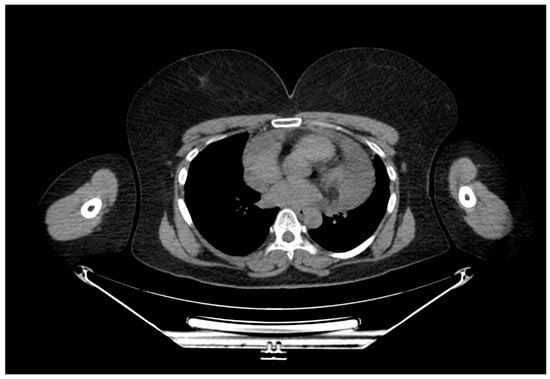

A Rare Case of Multilocular Mesothelial Inclusion Cysts of the Pericardium: Diagnosis, Treatment, Follow Up, with Comprehensive Review of the Literature

by Ali Shadmanian, Kosha Patel, Endre Alács, Henriette Gavallér, Szilva Agocs and Miklós Bitay

Background: Multilocular mesothelial inclusion cysts—also known as benign multicystic mesothelioma (BMM)—are rare, typically arising in the peritoneal cavity. Pericardial involvement is extremely uncommon and can pose diagnostic and therapeutic challenges due to their recurrent and infiltrative nature. Accurate diagnosis and surgical strategy are [...] Read more.

Background: Multilocular mesothelial inclusion cysts—also known as benign multicystic mesothelioma (BMM)—are rare, typically arising in the peritoneal cavity. Pericardial involvement is extremely uncommon and can pose diagnostic and therapeutic challenges due to their recurrent and infiltrative nature. Accurate diagnosis and surgical strategy are critical for management and recurrence prevention. Methods: We present the case of a 36-year-old woman with a prior history of malignant melanoma who developed recurrent multilocular cystic masses of the pericardium. Initial imaging with echocardiography, cardiac magnetic resonance (CMR), and computed tomography (CT) revealed multilocular pericardial cysts. Surgical resection was performed under cardiopulmonary bypass (CPB), but complete excision was limited due to epicardial infiltration. Histopathology confirmed a benign mesothelial origin. One year later, recurrence prompted a second surgical intervention with total pericardiectomy and Gore-Tex patch reconstruction. Results: Postoperative recovery was uneventful in both instances. Follow-up imaging at 6 and 12 months demonstrated no significant recurrence. Histological analysis confirmed benign cysts lined with mesothelial cells, positive for calretinin and WT-1. This represents one of the first documented living cases of pericardial BMM managed with staged surgery and total pericardiectomy. Conclusions: Pericardial BMM is a rare, benign, but potentially recurrent lesion. In cases of extensive or recurrent disease, total pericardiectomy may offer definitive treatment. Multimodal imaging, histopathological evaluation, and personalized surgical planning are essential for effective management. Full article

Figure 1